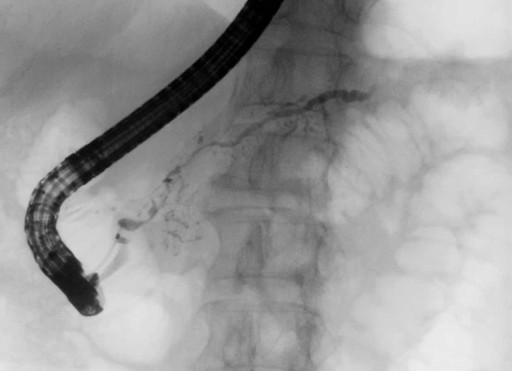

The patient was a 68-year-old woman who was admitted to our hospital due to liver function test abnormalities [7]. Endoscopic retrograde cholangiopancreatography (ERCP) revealed diffuse irregular narrowing in the head and body of the main pancreatic duct (Figure 1) and strictures of the hilar hepatic region and intrapancreatic bile duct. Abdominal computed tomography (CT) demonstrated diffuse enlargement of the pancreas. Four years after clinical onset, ERCP revealed longer strictures of the hilar hepatic region and intrapancreatic bile duct. In addition, the right lobe of the liver was atrophic. CT angiography revealed stenosis of the right branch of the portal vein. Laboratory tests showed elevation of the IgG4 level to 146 mg/dL (reference range: 4.8-105 mg/dL) and a positivity for antinuclear antibody with a titer of 1:320. The patient was diagnosed as having type 3 sclerosing cholangitis with autoimmune pancreatitis on the basis of our classification [2] and the Japanese diagnostic criteria for autoimmune pancreatitis [8]. However, steroid therapy was not initiated at the patient’s request [7].

Figure 1. Endoscopic retrograde cholangiopancreatography showing diffuse irregular narrowing in the head and body of the main pancreatic duct. |